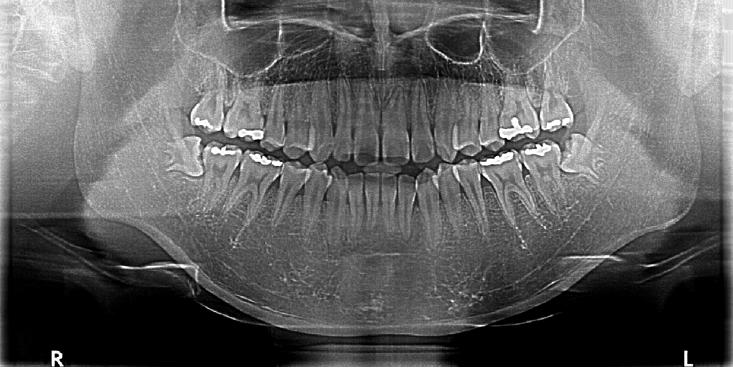

Intraoral examination revealed no significant abnormalities. Panoramic radiography showed impacted mandibular third molars (#38 and #48) bilaterally as shown in (Fig. 1).

Preoperative panoramic radiograph showing bilaterally impacted mandibular third molars without apparent bony pathology.